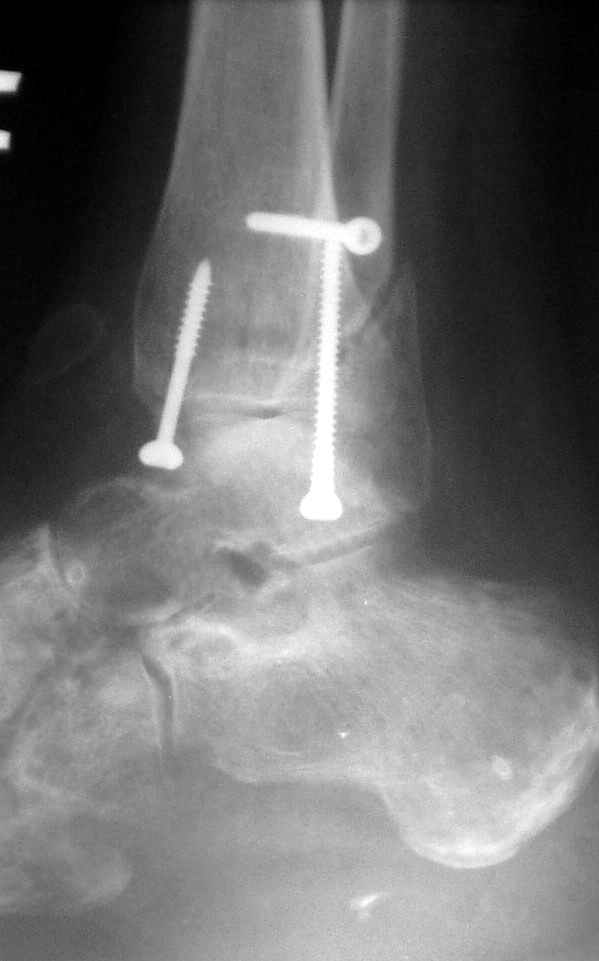

12 января прямой

12 января боковой

12 января трехчетвертной

Вариант с артродезом уже обсудили. Хотя, после увиденых снимков, пессимизм насчет восстановительной операции у меня, например, несколько уменьшился. Особенного уж какого-то остеопороза не видно даже на январских снимках. Можно черед мини-доступы убрать винты, аппаратом вправить малоберцовую кость, устранить подвывих стопы. Ну а дальше фиксировать малоберцовую пластиной сзади. А может, и напряженной Y-спицей попробовать - Анатолий Федорович, как Вы полагаете? Внутреннюю - то, что осталось, если уже не получится сделать спицами и проволокой, то что-то типа пластики дельтовидной связки. А может, и не трогать ее вовсе... В общем, выбор непростой,

много факторов надо взвесить.